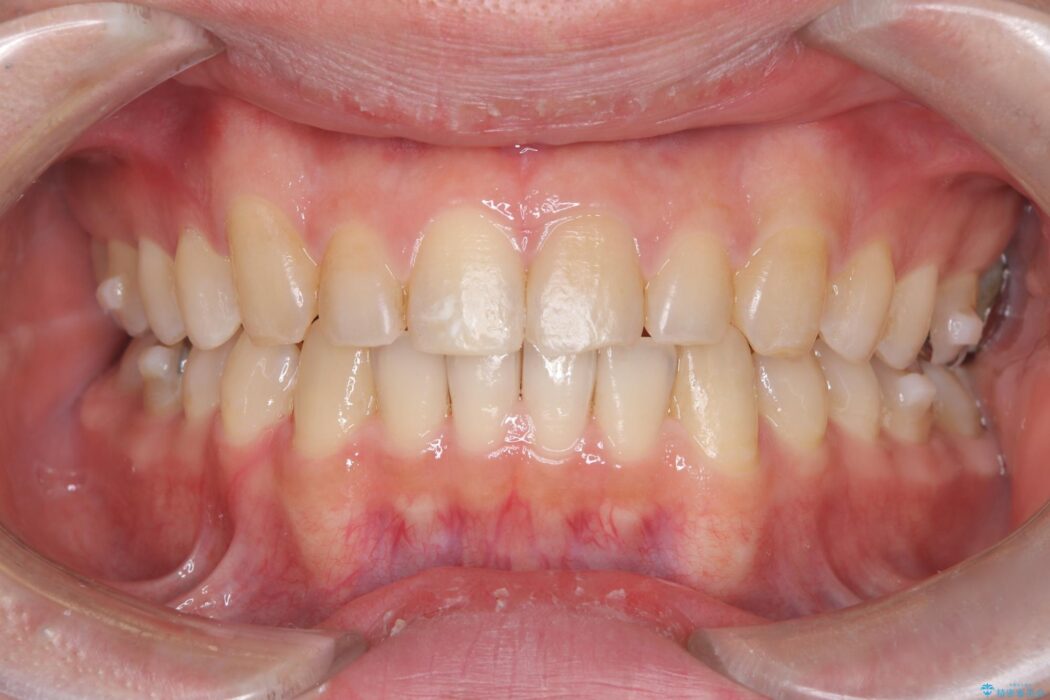

前歯の隙間とガタつきが気になるとご来院された患者様です。

正中離開・叢生のほかに、上下の奥歯が全く咬み合わないシザーズバイトの状態も認められました。